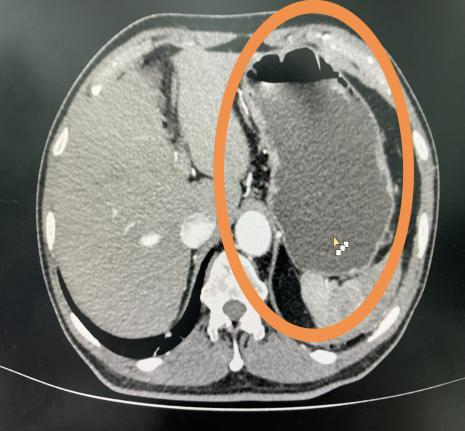

首先,对于某些特定部位的增强CT检查,如腹部或盆腔扫描,放射君在之前也和大家科普过,检查前的大量饮水能使胃肠道充盈,从而更好地区分各种腹部组织和器官。这种自然对比的效果,可以提高图像的对比度,使得潜在的问题区域更加突出,从而有助于医生作出更精确的诊断。

饮水前                                   饮水后